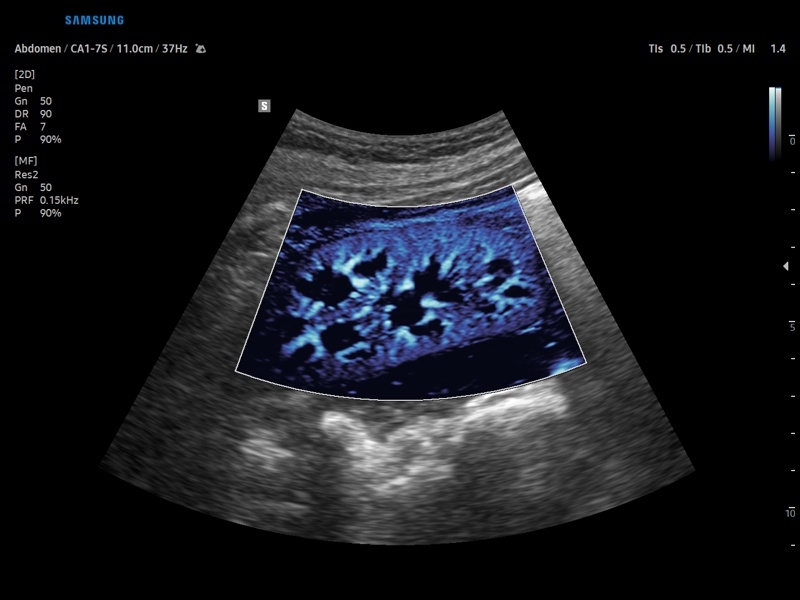

• Контрастное усиление CEUS+

• Модуль CEUS+ (Contrast Enchansment UltraSound) - программа, позволяющая проводить обследование с применением контрастных агентов.

• Модуль MV-Flow – программа (режим), позволяющая визуализировать кровоток в микроциркуляторном русле с высоким разрешением без использования контраста.